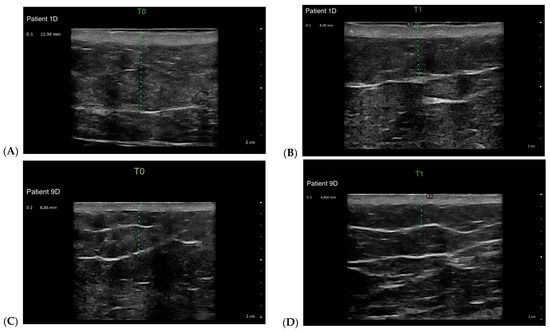

Multiple Calcaneus Secundarius Ossicles Presenting with Anterior Foot Pain: A Case Report Highlighting Characteristic Imaging Features

by Ki Jin Jung, Eui Dong Yeo, Jeong Han Nam and Woo Jong Kim

Background: Calcaneus secundarius (CS) is an accessory ossicle located at the anterior aspect of the calcaneus and is typically an incidental and asymptomatic radiographic finding. However, it may become symptomatic following trauma or repetitive mechanical stress and can mimic anterior calcaneal process [...] Read more.

Background: Calcaneus secundarius (CS) is an accessory ossicle located at the anterior aspect of the calcaneus and is typically an incidental and asymptomatic radiographic finding. However, it may become symptomatic following trauma or repetitive mechanical stress and can mimic anterior calcaneal process fracture or tarsal coalition, leading to diagnostic confusion. The presence of multiple independent CS ossicles represents a rare morphological variant and a potential source of diagnostic ambiguity. Methods: We report the case of a 19-year-old male soldier who presented with progressive anterior foot pain following soccer activity without a clearly identifiable traumatic event. Radiographs, computed tomography (CT), and magnetic resonance imaging (MRI) were performed to evaluate the underlying pathology. Results: CT demonstrated two separate, well-corticated accessory ossicles adjacent to the anterior calcaneal process without bony continuity. MRI revealed focal bone marrow edema (BME) at the calcaneus–ossicle interface, suggesting mechanical irritation at the fibrous connection. Due to persistent symptoms and concordant imaging findings, surgical excision was performed, resulting in immediate pain relief and return to full daily and sports activities without recurrence at the 1-year follow-up. Conclusions: Multiple CS ossicles may produce fragment-like imaging appearances and increase the risk of misdiagnosis. Recognition of characteristic imaging features, particularly well-corticated ossicles and focal BME at the ossicle–calcaneus interface, together with clinical correlation, is essential for accurate diagnosis and appropriate management in patients with persistent anterior foot pain. Full article

Figure 1